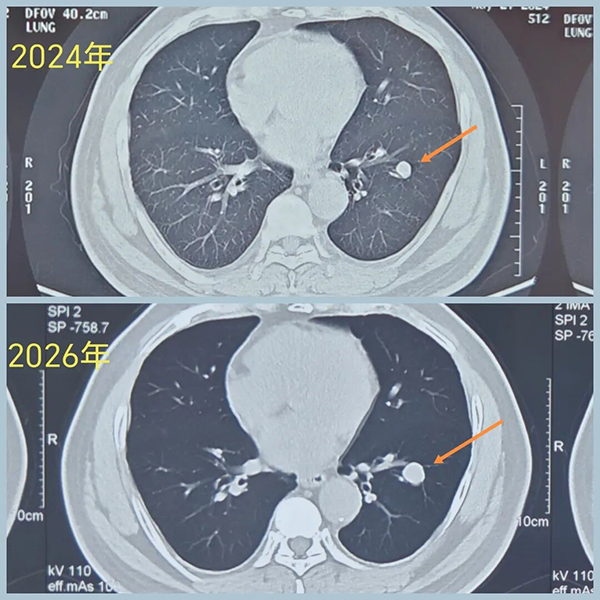

男性,40+岁,发现左下叶实性结节5年

患者诉结节刚发现时为0.8cm,形态像良性,给予定期复查

后结节逐渐增大

2026年3月CT示病变1.6cm

(再早片子无法追溯,只能对比24年的片子。)

术前CT示:左肺下叶基底段实性结节,大小1.6cm,边界清,有浅分叶,内部密度不均,有点状高密度。看形态确实像良性。